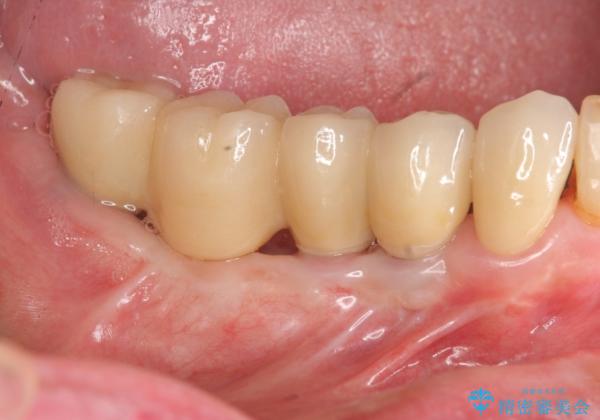

奥歯のインプラント治療

- 奥歯を失い噛めない、しっかりと噛めるようになりたいと希望され来院されました。

清掃性に優れたジルコニアカスタムアバットメント、ジルコニアクラウンを用いて機能性だけでなく審美性・予知性を高めます。

- 130万円(HAインプラント×3・骨造成・ジルコニアカスタムアバットメント×3・ジルコニアクラウン×4)費用は治療当時の料金となります